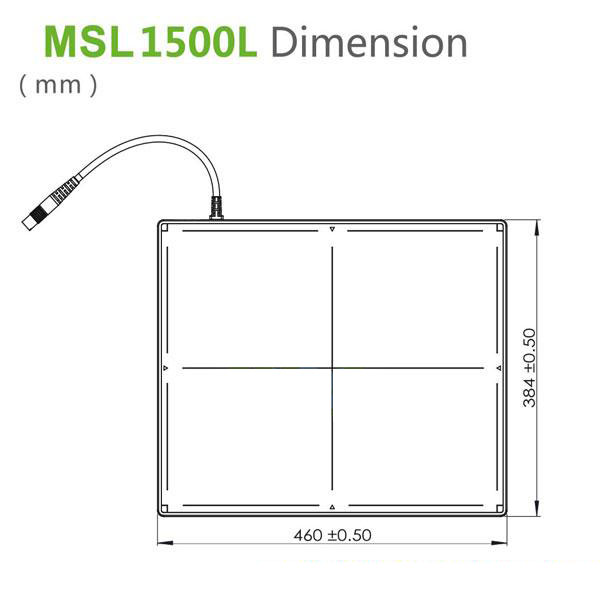

Detector de radiografía multipropósito B.S.D.500L en venta  Características del detector de radiografía multipropósito B.S.D. B.S.D.1500L El detector multipropósito 1500L de 14″ X 17″ (384 460 15 mm³) está diseñado para cumplir con una amplia gama de requisitos para aplicaciones de radiografía digital, por ejemplo, modernización de sistemas de radiografía existentes (p. ej., CCD-DR, CR y película), integración con sistemas de montaje fijo y también varios sistemas DR móviles y portátiles. La tecnología más avanzada de deposición directa de CsI garantiza una excelente calidad de imagen con bajas dosis de rayos X y mejora la seguridad operativa. Sus múltiples modos de sincronización ofrecen flexibilidad universal para fabricantes e integradores de sistemas. El exclusivo detector F²AED™ (Detector Automático de Exposición de Campo Completo) Detectoe ofrece una cobertura completa del área de imagen y una baja sensibilidad a la dosis para un funcionamiento fiable en situaciones difíciles. Su bajo consumo de energía, su diseño de eficiencia térmica y la conexión con un solo cable facilitan la instalación y el funcionamiento del B.S.D.1500L. B.S.D.1500L combina a la perfección un rendimiento robusto y una excelente relación calidad-precio.

Características del detector de radiografía multipropósito B.S.D. B.S.D.1500L El detector multipropósito 1500L de 14″ X 17″ (384 460 15 mm³) está diseñado para cumplir con una amplia gama de requisitos para aplicaciones de radiografía digital, por ejemplo, modernización de sistemas de radiografía existentes (p. ej., CCD-DR, CR y película), integración con sistemas de montaje fijo y también varios sistemas DR móviles y portátiles. La tecnología más avanzada de deposición directa de CsI garantiza una excelente calidad de imagen con bajas dosis de rayos X y mejora la seguridad operativa. Sus múltiples modos de sincronización ofrecen flexibilidad universal para fabricantes e integradores de sistemas. El exclusivo detector F²AED™ (Detector Automático de Exposición de Campo Completo) Detectoe ofrece una cobertura completa del área de imagen y una baja sensibilidad a la dosis para un funcionamiento fiable en situaciones difíciles. Su bajo consumo de energía, su diseño de eficiencia térmica y la conexión con un solo cable facilitan la instalación y el funcionamiento del B.S.D.1500L. B.S.D.1500L combina a la perfección un rendimiento robusto y una excelente relación calidad-precio.

El mejor detector de radiografía multipropósito B.S.D.1500L Especificaciones Sensor Centelleador Depósito directo de CsI Área activa 434 x 355 mm² (14″x17″) Matriz de píxeles 2816X2304 Paso de píxeles 154 μm Calidad de imagen Resolución límite 3,3 lp/mm MTF >70 %……(@1 lp/mm) >40 %……(@2 lp/mm) >22 %……(@3 lp/mm) DQE >65 %……(@0 lp/mm) >20 %……(@3 lp/mm) Sensibilidad ~0,62 ct/nGy Dosis lineal máxima 95 Gy Rango dinámico >82 dB Escala de grises 16 bits Interfaz de comunicación Interfaz de comunicación Gigabit Ethernet Tiempo de adquisición de imágenes 2-3 s Control de exposición F²AED™ Manual Ambiental Funcionamiento Enfriamiento natural Rango de temperatura 5 ℃-35 ℃ (41 ℉-95 ℉) Rango de humedad (sin condensación) 30 %-75 % HR Rango de temperatura de almacenamiento -20 ℃-55 ℃ (-4 ℉-67 ℉) Rango de humedad 10 %-90 % HR Mecánico Dimensiones 384 x 460 x 15 mm3 (15″ x 18″ x 0,6″) Peso 3,4 kg Material de la carcasa Parte frontal de fibra de carbono Parte trasera de aleación de aluminio de alta resistencia Potencia Disipación de potencia 8 W (en espera) 20 W (en funcionamiento) Fuente de alimentación 100-240 V CA Frecuencia 50/60 Hz Regulador FDA *(En progreso) CE HD60077005 0001 UL E464810

El mejor detector de radiografía multipropósito B.S.D.1500L Especificaciones Sensor Centelleador Depósito directo de CsI Área activa 434 x 355 mm² (14″x17″) Matriz de píxeles 2816X2304 Paso de píxeles 154 μm Calidad de imagen Resolución límite 3,3 lp/mm MTF >70 %……(@1 lp/mm) >40 %……(@2 lp/mm) >22 %……(@3 lp/mm) DQE >65 %……(@0 lp/mm) >20 %……(@3 lp/mm) Sensibilidad ~0,62 ct/nGy Dosis lineal máxima 95 Gy Rango dinámico >82 dB Escala de grises 16 bits Interfaz de comunicación Interfaz de comunicación Gigabit Ethernet Tiempo de adquisición de imágenes 2-3 s Control de exposición F²AED™ Manual Ambiental Funcionamiento Enfriamiento natural Rango de temperatura 5 ℃-35 ℃ (41 ℉-95 ℉) Rango de humedad (sin condensación) 30 %-75 % HR Rango de temperatura de almacenamiento -20 ℃-55 ℃ (-4 ℉-67 ℉) Rango de humedad 10 %-90 % HR Mecánico Dimensiones 384 x 460 x 15 mm3 (15″ x 18″ x 0,6″) Peso 3,4 kg Material de la carcasa Parte frontal de fibra de carbono Parte trasera de aleación de aluminio de alta resistencia Potencia Disipación de potencia 8 W (en espera) 20 W (en funcionamiento) Fuente de alimentación 100-240 V CA Frecuencia 50/60 Hz Regulador FDA *(En progreso) CE HD60077005 0001 UL E464810